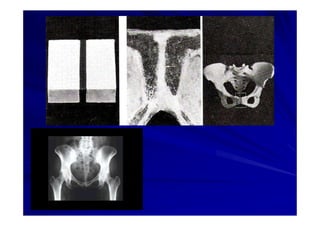

El documento presenta una introducción a la anatomía normal. Explica que la anatomía es el estudio de la estructura del cuerpo humano y clasifica los tipos de anatomía. Además, enumera los contenidos que serán cubiertos en el curso, incluyendo conceptos, posición anatómica, vocabulario, osteología, artrología y miología.